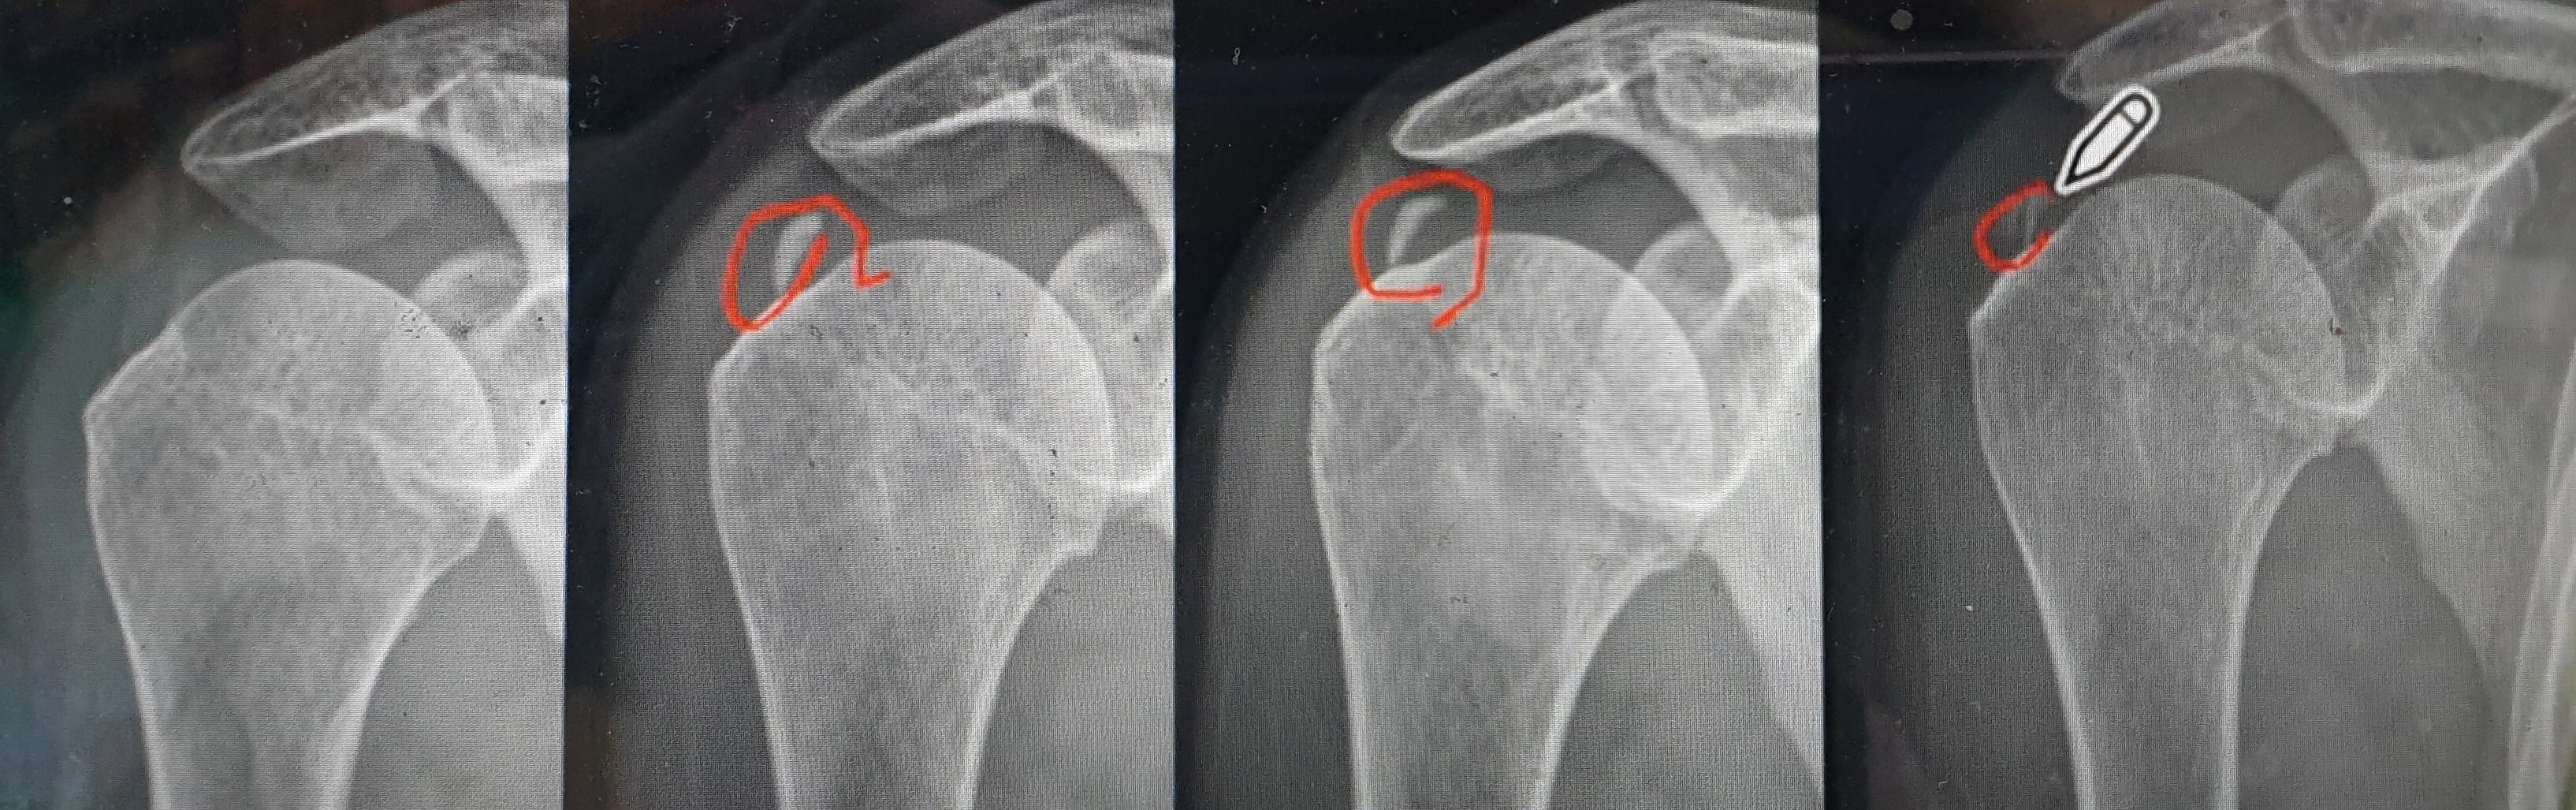

위 사진의 맨 왼쪽처럼 처음에는 어깨 힘줄 부위에 아무것도 없는 깨끗한 상태이다가 어느 순간 석회 결절이 생기게 되고 그것이 점점 줄어 마지막에는 몸에 흡수되어 사라지게 됩니다. 더 자세한 석회결절의 변화과정을 알아보기 위해서 회전근개 힘줄을 중심으로 한 석회결절의 일생을 보겠습니다.

위 사진상 화살표 방향으로 회전근개 힘줄 안에 석회결절이 시간이 지남에 따라서 변화하게 됩니다.

깨끗하던 회전근개 힘줄에 단단한 석회결절이 생기고 그 단단하던 석회결절이 시간이 지나며 차츰 녹기 시작하는데 녹아내리는 과정에서 크기도 부풀어지며 커지고 위치도 피부 쪽으로 이동하는 양상을 보이게 됩니다.(사진의 두 번째에서 세 번째 단계)

그러다가 조각이 나거나 (사진의 네 번째 단계) 터져 나오기도 하고(사진의 다섯 번째 단계) 아주 작은 조각들로 산산조각 나 부서져(사진의 여섯 번째 단계) 내리기도 합니다. 몇 년의 시간이 경과하면 차츰 녹아내리며 (사진의 일곱 번째 단계) 우리 몸으로 점점 흡수되어 예전에 석회가 없던 정상힘줄로 바뀌게 되는 것(사진의 여덟 번째 단계)입니다.